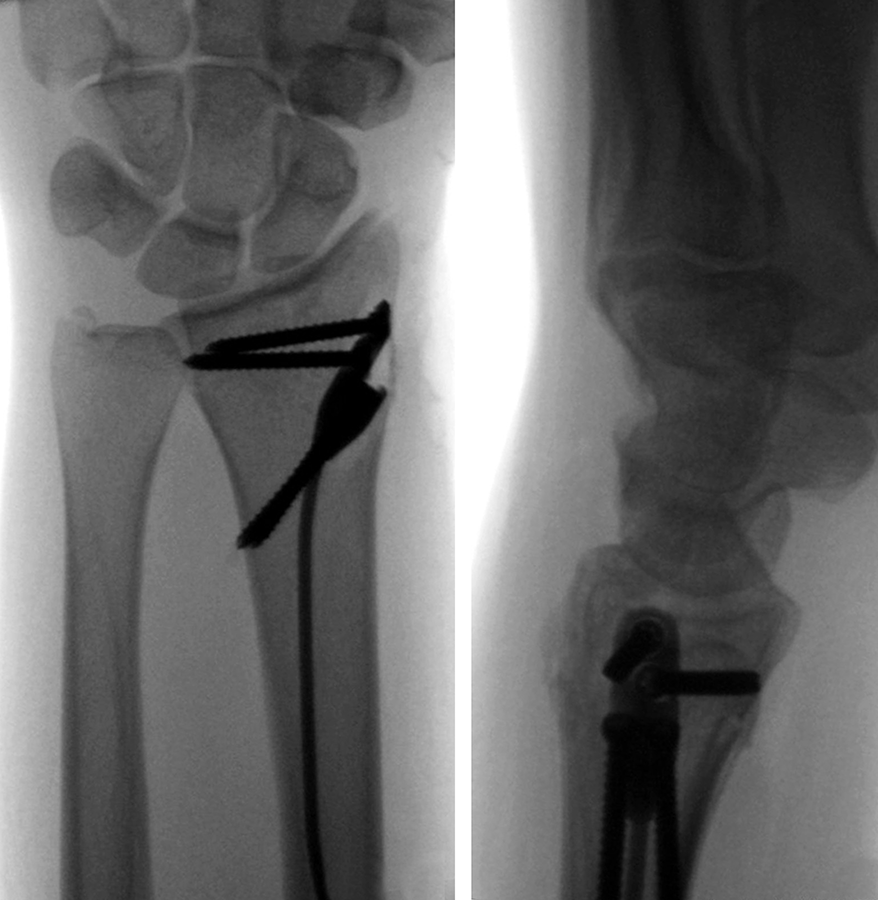

In response to such potential complications in the fixation of extraarticular distal radius fractures, a collaboration between the University of Balgrist, Disrad AG, the AO Technical Commission Hand Expert Group, the AO's Development Incubator, and 41medical has witnessed the design and development of an intramedullary implant. With the advent of this new device, a decrease in soft-tissue complication is expected. The implant utilizes the principles of load sharing, subchondral screw divergence, and locked fixed-angle fixation. The intramedullary implant is inserted through a small skin incision at the radial styloid and does not further devascularize the fracture fragments. The limited surgical dissection and rigid fracture fixation allows for minimal postoperative mobilization and an early return to function. The newly approved DRIM-Nail is a valuable addition to the arsenal of distal radius fracture treatment options, which can rapidly have patients on the path to recovery.

Finding an industrial partner for the AO-approved DRIM-Nail is ongoing (as of November 2022). The nail is 7.0 mm in diameter and single packed as a 'one size fits all' sterile implant. The nail itself is made from titanium and the additional 2.5 mm diameter screws for fixation (ranging from 14−36 mm) are made of stainless steel (Fig 3). The instrument set is lean but comprehensive and intuitive to use. All instruments are nonsterile and validated according to 41medical reprocessing.

After closed reduction a dorsal re-dislocation of 25° occurred (Fig 4a). There are additional apparent signs of instability: dorsal comminution (Fig 4a) and fracture of the ulnar styloid (Fig 4b). Therefore, a considerable potential for further dislocation is present which is likely to occur in a cast. This young, active, and demanding patient wishes to return to her activities as early as possible. This can only be achieved with an operative fracture fixation. The nail was chosen instead of a plate. This allowed an almost instant functional use of her hand, which allowed her to return to work at 2 weeks postoperatively without additional fixation or a splint and full unprotected function of her wrist at 6 weeks.